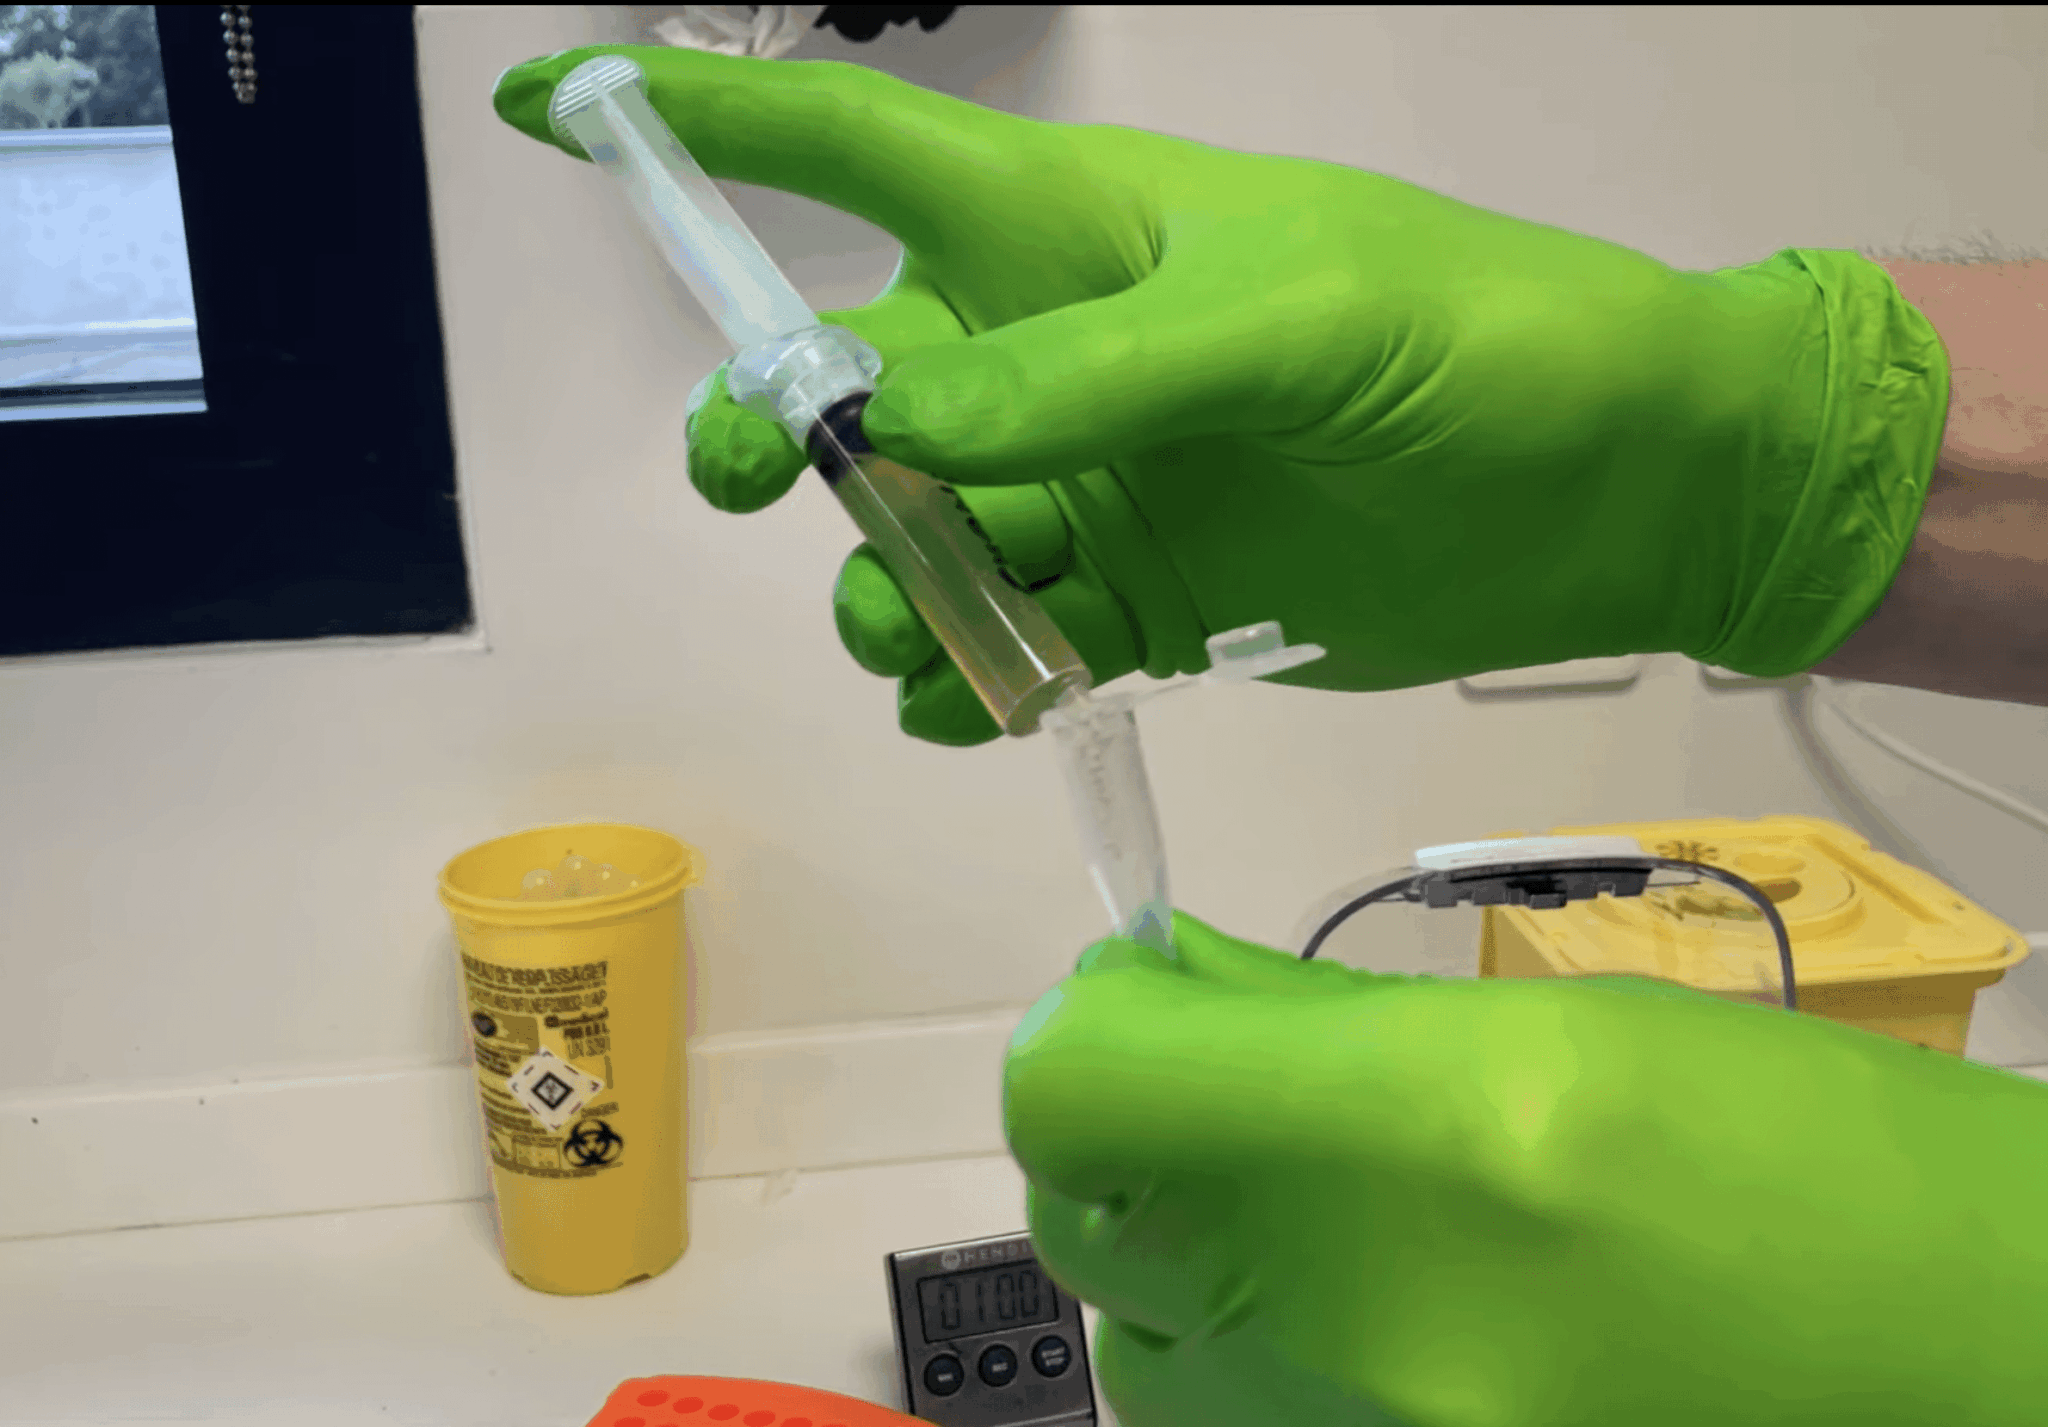

Réaliser un culot urinaire

Le Dr Benoit Rannou vous explique comment réaliser un culot urinaire en images commentées. Lire la suite